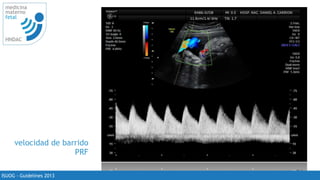

velocidad de barrido

PRF

corregido